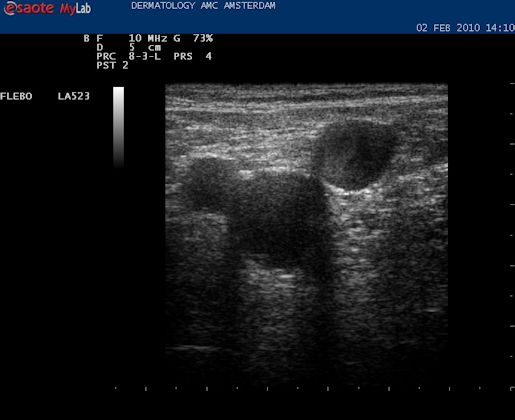

| Met de echokop dwars op de binnenkant van het bovenbeen wordt direct een hooggelegen (extrafasciaal gelegen) vena saphena magna gezien. De VSM wordt in het midden van het beeld geplaatst. |

| Daarna de echokop draaien in de lengte richting van het vat. Nu is het mooi helemaal in beeld. |

| De volgende stap is om de VSM te vervolgen naar de oorsprong in de lies, daar waar de VSM ontspringt uit de vena femoralis superficialis. Hiervoor proberen we de Mickey Mouse figuur in beeld te krijgen die hier boven te zien is. Vaak verschijnt dat al als de echokop in de liesplooi wordt gezet. Met de markering op de kop naar boven lateraal. Dan is het vat in het midden de vena femoralis. Het linker oortje, kleinere diameter, is de arterie, en het rechter oortje is de vena saphena magna. |

| Anatomie liesplooi. Lichtblauw: vena femoralis, diep systeem. Donkerblauw: vena saphena magna, oppervlakkig systeem. Rood: arteria femoralis. In de liesplooi precies waar de VSM aftakt vormen deze drie vaten de Mickey Mouse figuur. Als de echoknop markering naar lateraal staat is het rechteroortje altijd de VSM. |